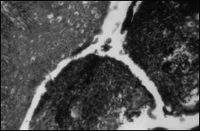

разрастании соединительной ткани, образовании обширных соединительнотканных тяжей, иногда с признаками гиалиноза (рис.17). Обнаруживались также очаги гнездных инфильтратов, состоящие из лимфоидных и плазматических клеток, главным образом вокруг мелких сосудов (рис. 18). Выявлялись изменения со стороны кровеносных сосудов в миндалинах, преимущественно в капелле, окружающей миндалину перипаратон- зилляриой ткани, в трабекулах. Сосуды при этом резко расширены, с признаками выраженного ва- скулита. Выявлялись сосуды, у которых просветы полностью закрыты за счет набухания и пролиферации эндотелия (рис. 9,20), средней и наружной оболочек. Обращает на себя внимание также частота склероза мелких сосудов и нередко их гиалинизация (рис.21).

Рис. 19. Расширенные сосуды. Окраска гематоксилин-эозин, ув. x 400 |

Рис. 20. Набухание и пролиферация эндотелия. Резкое сужение просвета сосудов. Окраска гематоксилин-эозин,ув. x 400 |